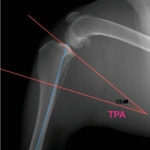

TPLOはSlocumが提唱した前十字靭帯断裂に対する手術法であり、脛骨高平部を水平に回転させる骨きり術によって、体重負重時の脛骨の前方変位を抑制し、膝関節を安定化します。犬の脛骨高平部の角度(Tibial plateau angle:TPA)は約25°と言われており、この角度を約6.5°に矯正すると脛骨の前方変位が抑えられ、膝関節が安定します。世界的にも手術成績が安定している術式です。

本症例は、走った後に左後肢を挙上していることを主訴に来院されました。触診時に左膝関節のクリック音を聴取、レントゲン検査にて左脛骨の前方変位が認められました。術中に、前十字靱帯の断裂及び内側半月板の損傷、内側の軟部組織の顕著な腫脹を確認。半月板切除、TPLOを実施しました。周囲組織への炎症の波及もあったため回復に時間を要しておりますが、徐々に跛行頻度は減少傾向にあり、現在も経過観察中です。術前に約29°あったTPAは術後に約10°まで矯正されました。

手術前後のTPA(脛骨高平部の角度)を測定しています。

約29°から約10°へ矯正されています。

レントゲン検査 にて

脛骨公平部角(TPA)の急峻を認める

手術前TPA 28.4° が術後TPA 11.7° に矯正されました。

術前TPA計測

手術前

術後TPA計測

手術後